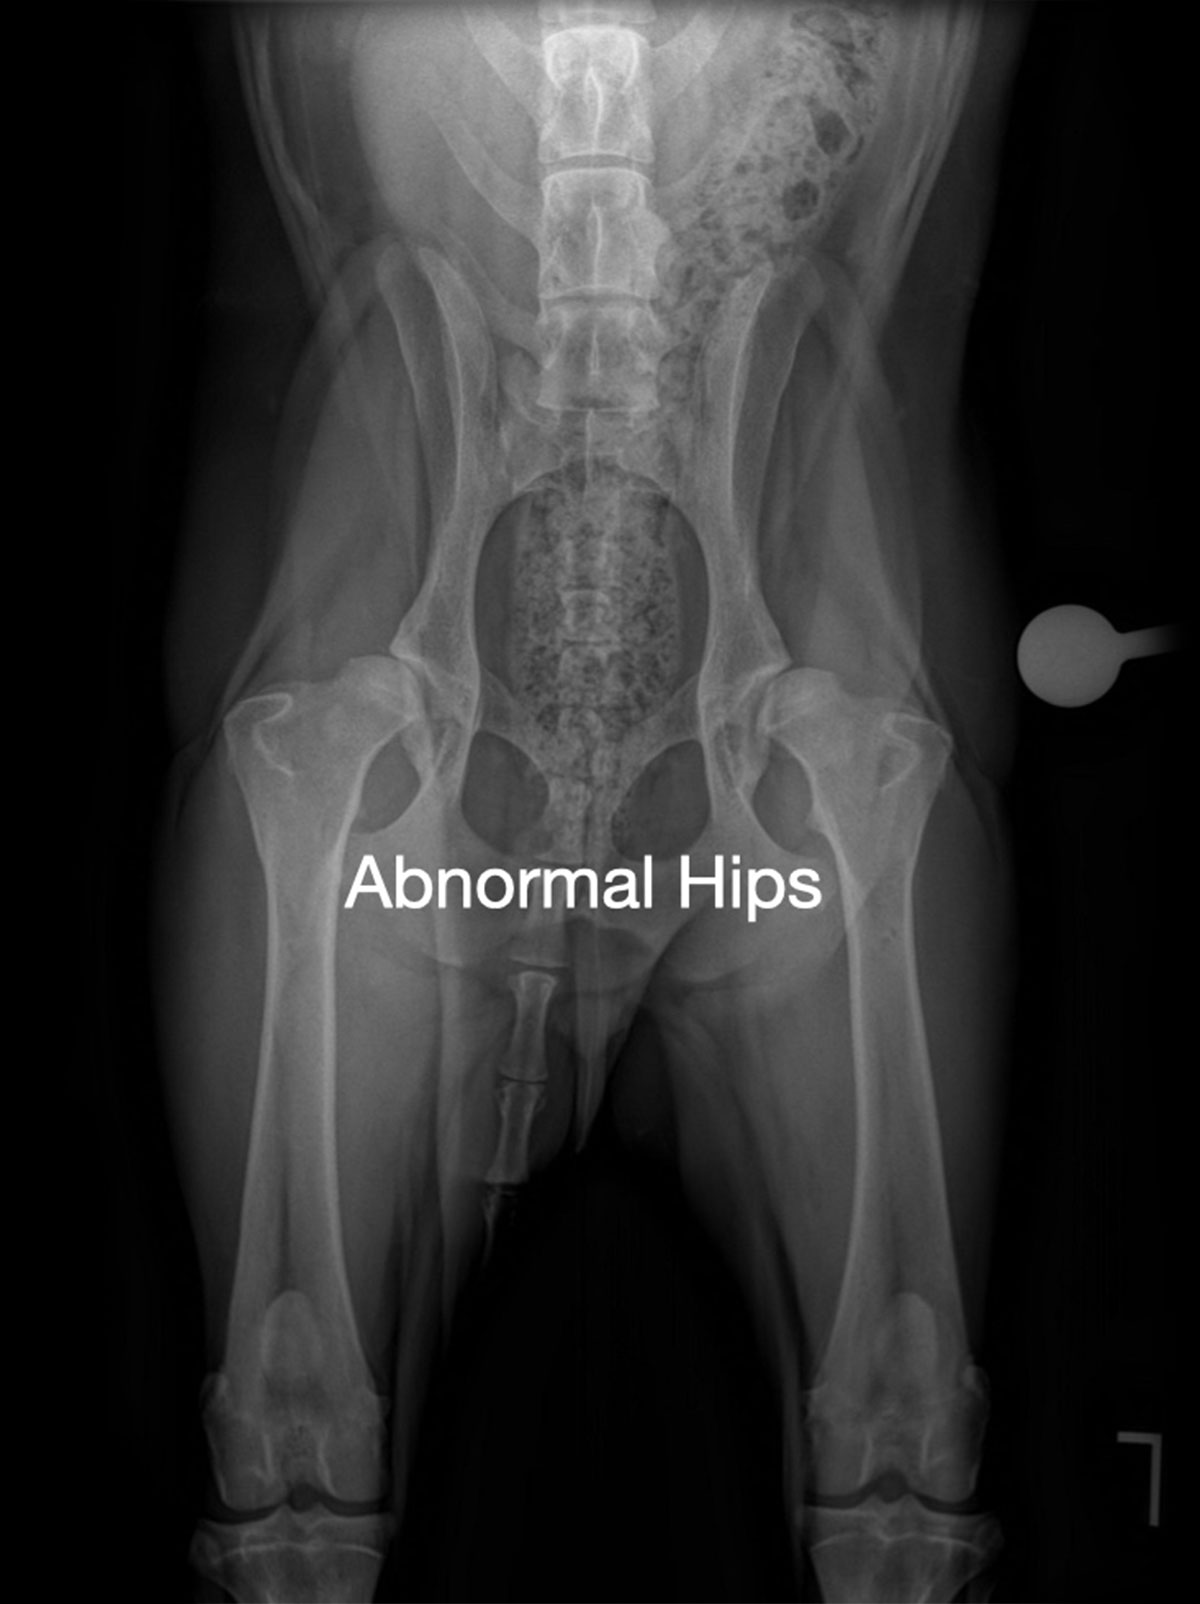

Hip dysplasia, one of the most common orthopedic conditions in dogs, refers to the abnormal formation of the ball-and-socket joint of the hip. When these bones fit together more loosely than they should, the joint has more movement than normal. This looseness (called joint laxity) can lead to instability, osteoarthritis (OA), pain and lameness.